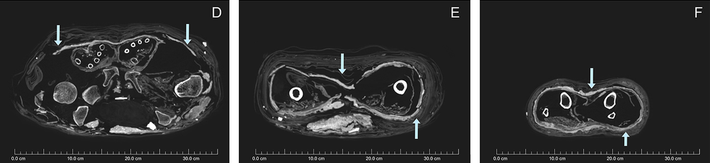

Gần đây, nhà khảo cổ Karin Sowada (Đại học Macquarie, Australia) dẫn đầu một nhóm chuyên gia có phát hiện lớn. Nhóm của ông phát hiện xác ướp được bọc bằng bùn trông như chiếc kén. Đây là điều rất hiếm gặp.

Sau khi qua đời, người phụ nữ được ướp xác và quấn nhiều lớp vải. Thi hài này đầu gối trái và cẳng chân bị phá hủy có thể là do những tên trộm mộ gây ra. Vì vậy, con cháu của người chết đã bọc lại xác ướp và trát bùn xung quanh.

Lần này, những người thợ dùng hỗn hợp phức tạp gồm bùn, cát và rơm giữa các lớp vải quấn bằng lanh. Lớp phủ nền có chất tạo màu từ calcite trắng trong khi lớp trên cùng phủ đất son, một loại khoáng chất màu đỏ.

Khi trát lên xác ướp, lớp bùn vẫn còn ẩm và dễ uốn nặn. Từ đó, xác ướp có hình dáng giống chiếc kén.